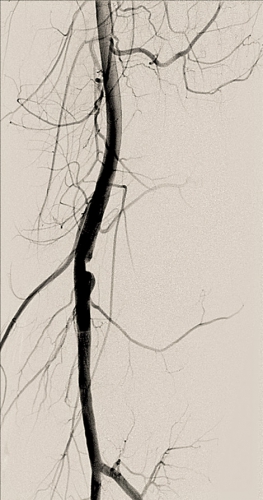

Diagnosen ställs med duplexundersökning eller angiografi. Man bör göra en dynamisk undersökning då patienten plantarflekterar i fotleden i liggande ställning eller ställer sig på tå, varvid det mediala gastrocnemius-huvudet och senan sträcks med ocklusion av artären (Figur 1). Behandlingen är öppen operation med bakre åtkomst där komprimerande strukturer delas. Eventuellt behöver den förlängda artären förkortas, och om sekundära degenerativa förändringar eller poststenotisk aneurysmutveckling föreligger kan en vengraft behöva sys in.